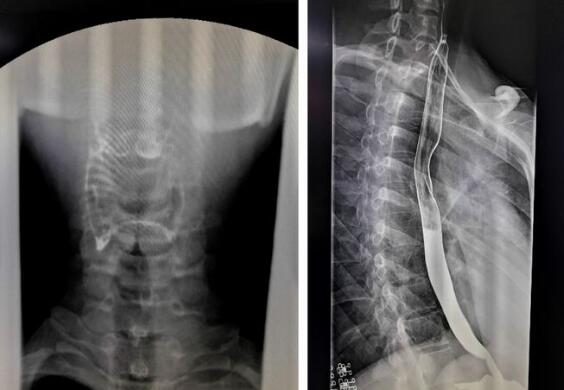

數字化胃腸機拍攝的上消化道造影圖

1、上消化道造影,能顯示咽部到十二指腸的影像。